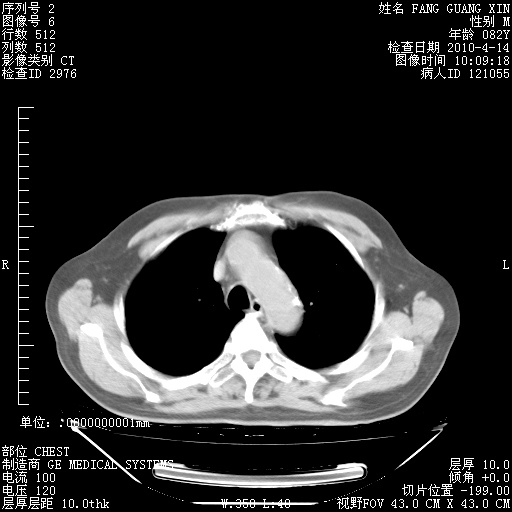

4月14日肺部CT

23.JPG

24.JPG

25.JPG

26.JPG